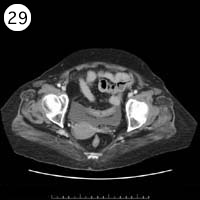

57歳 女性

単純CT

造影CT

※異常画像を赤枠で示しています